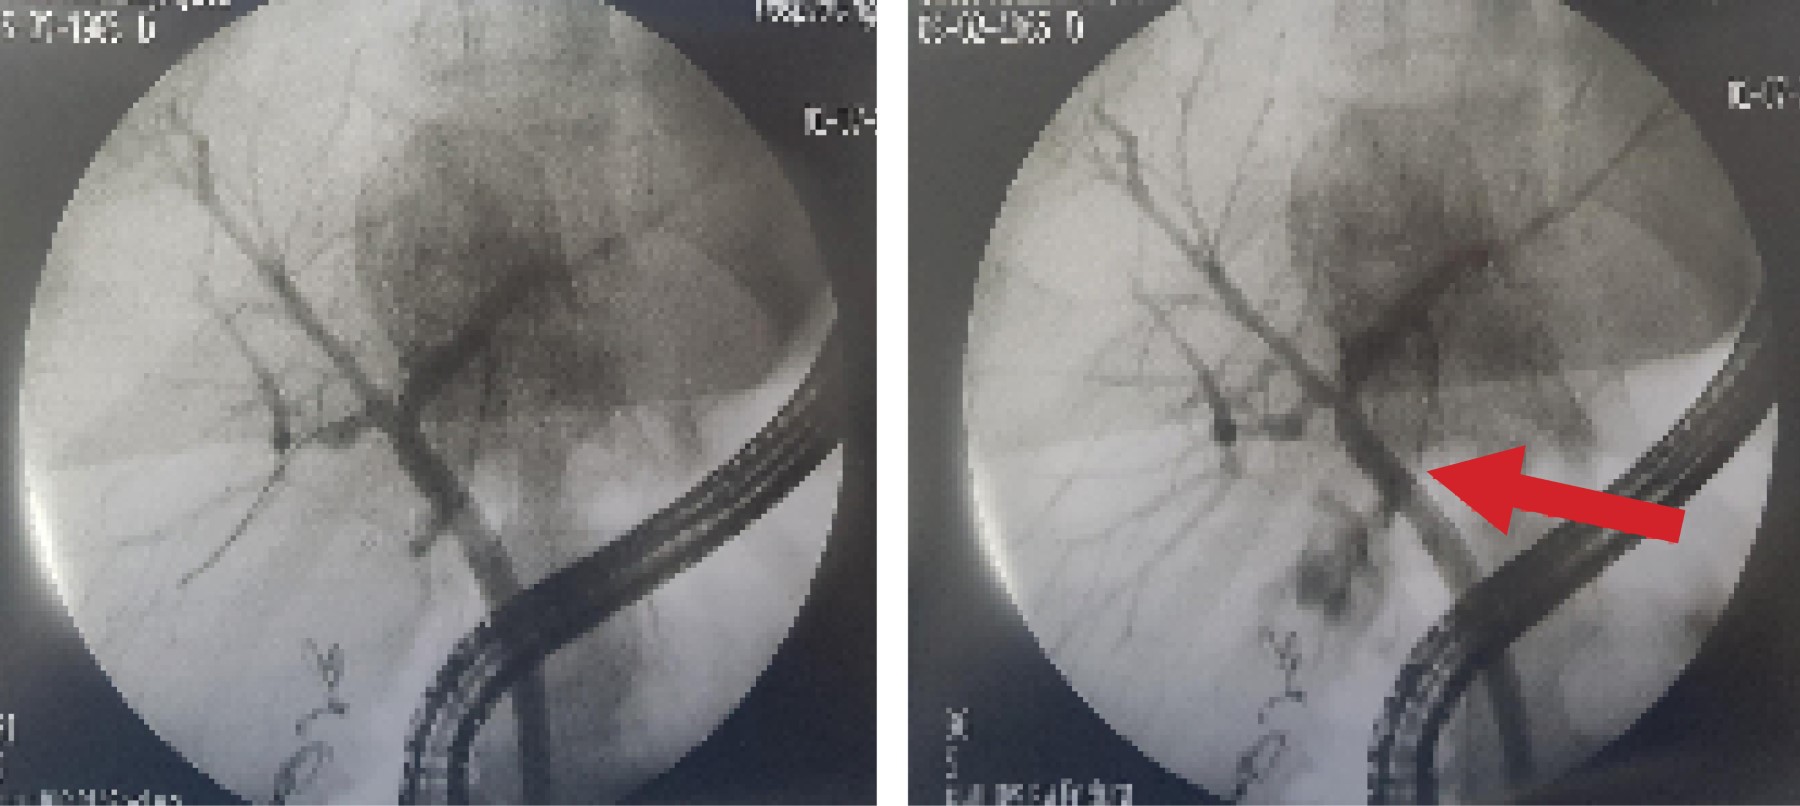

Introduction: laparoscopic cholecystectomy is the gold standard for gallstone disease, however, it is not free of complications, such as hemorrhage, seroma, biloma, biliary leakage, surgical wound infection and bile duct injury, being the presence of aberrant ducts one of the main risk factors. The anatomical variations of the biliary tract are due to alterations in the embryological development, it is important that the surgeon knows how to recognize them, since during cholecystectomy there is a risk of ligation, section, biliary leak or stenosis of an accessory or aberrant duct. Biliary leaks have increased since the standardization of laparoscopic cholecystectomy, with a frequency of approximately 0.3-0.5%. Endoscopic retrograde cholangiopancreatography (ERCP) is the ideal study, since it confirms the diagnosis by identifying the site of biliary leakage and during the same procedure sphincterotomy and stent placement can be performed, allowing closure of the defect, with a success rate of more than 90%. Clinical cases: we present two cases of biliary leakage after laparoscopic cholecystectomy secondary to the presence of anatomical variations of the extrahepatic biliary tract, both manifested by abdominal pain requiring hospitalization. In the first case the biliary leak was evidenced during ERCP and was resolved with the placement of a stent. The other case, having a negative ERCP and persistence of abdominal pain, underwent diagnostic laparoscopy, finding a biliary leak from an accessory duct, for which a new transoperative ERCP was performed for stent placement. Conclusion: these two cases are very interesting because despite being the same type of biliary leak, they presented differently, one at 72 hours postoperatively and the other at eight days. Likewise, one of them was resolved by ERCP and the other had a negative ERCP before the definitive diagnosis could be made. Therefore, a high index of suspicion of biliary leakage through an accessory or aberrant duct should be taken into account when faced with abdominal pain after laparoscopic cholecystectomy.

Figure 3